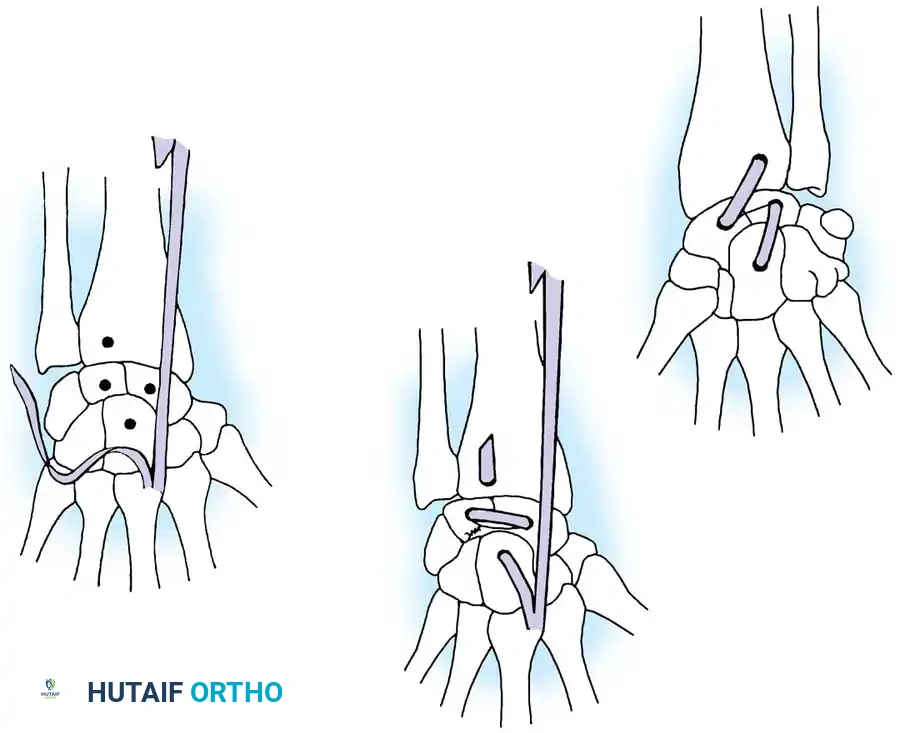

Surgical Management of Scapholunate Dissociation

Acute Injuries (<4 weeks):

Closed reduction with percutaneous pinning (placing 0.045-inch K-wires from the scaphoid to the capitate and lunate) can be attempted. However, open reduction through a dorsal approach is generally preferred. This allows direct closure of the scapholunate gap, K-wire fixation, and primary repair of the dorsal SL interosseous ligament using suture anchors.